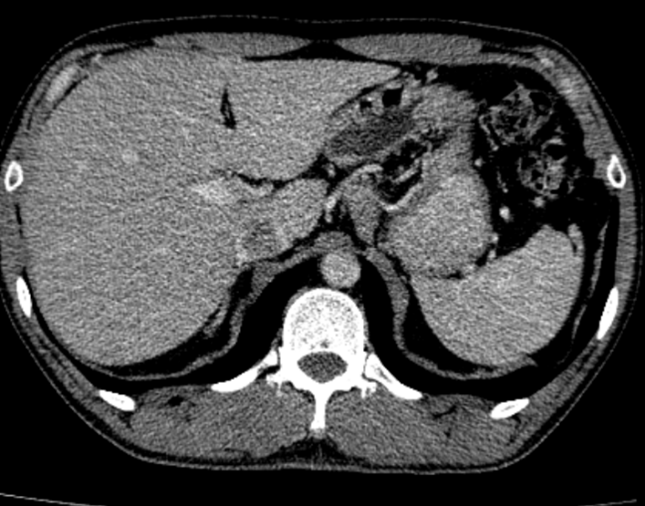

- CT ổ bụng:

Hình 3. Trên phim chụp CT ổ bụng: Nhu mô gan sát bao gan phân thùy S5 có nốt giảm tỷ trọng trước tiêm, ngấm thuốc kém sau tiêm, đường kính 10mm – Theo dõi tổn thương thứ phát. Dày tuyến thượng thận trái.

Trên phim chụp cắt lớp vi tính ổ bụng:

Trước điều trị:

Sau 3 tháng điều trị: Tổn thương gan và thượng thận đã biến mất.

Hiện tại trong quá trình theo dõi gan và thượng thận 2 bên vẫn chưa xuất hiện tổn thương mới.